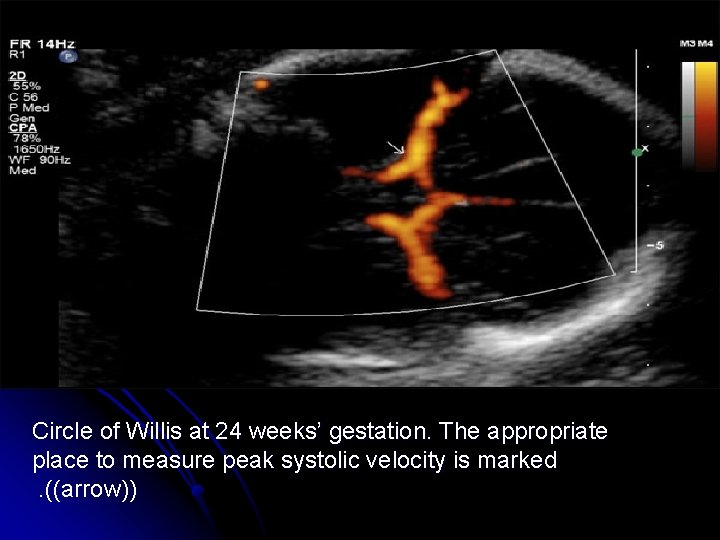

-Doppler assessment of peak velocity in the fetal middle cerebral artery MCA may prove to be the most valuable ultrasonic tool for detecting fetal anemia. - After 35 week gestation , this test may produce a higher false-positive rate.

Circle of Willis at 24 weeks’ gestation. The appropriate place to measure peak systolic velocity is marked. ((arrow))